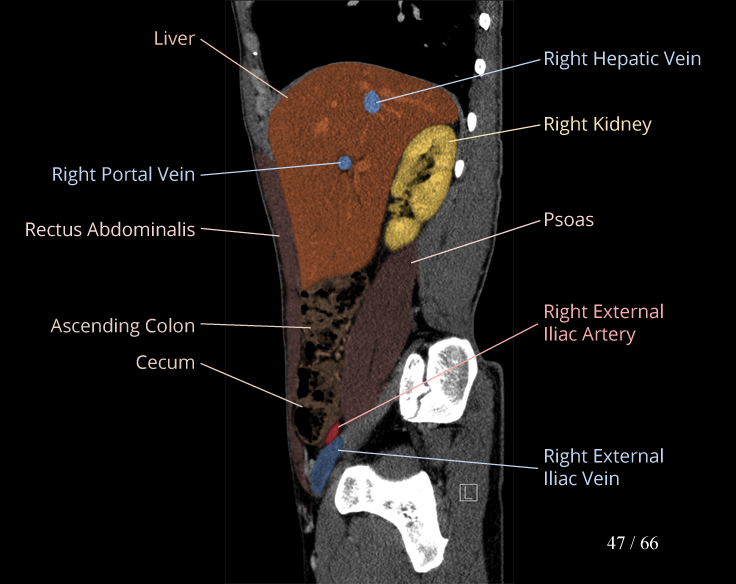

Anatomy Modules

Labeled radiographs and scrollable CT/MRI series teaching radiologic anatomy with a level of detail appropriate for medical students and junior residents.

Body

Covers abdominal CT anatomy.